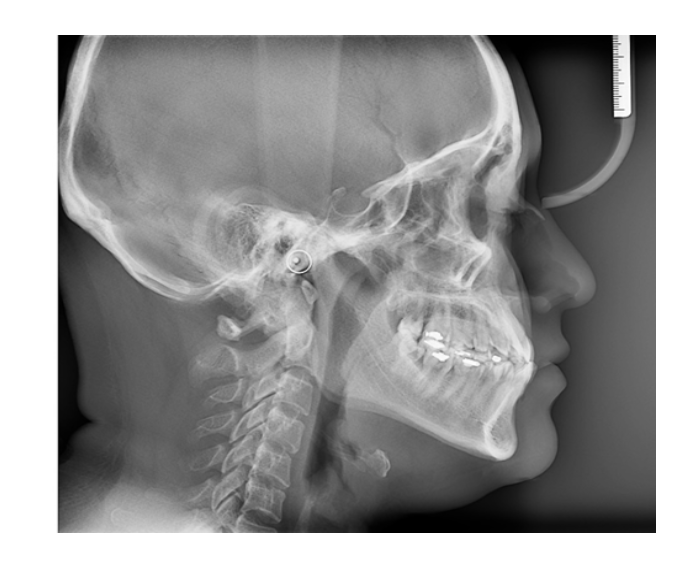

- Cefalométricas

- Tomografías